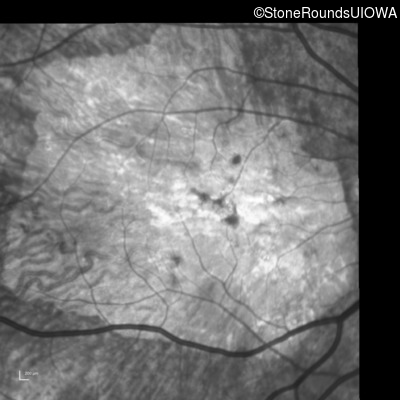

Infrared Fundus Photograph - Right - 20/250 sc

Exemplar